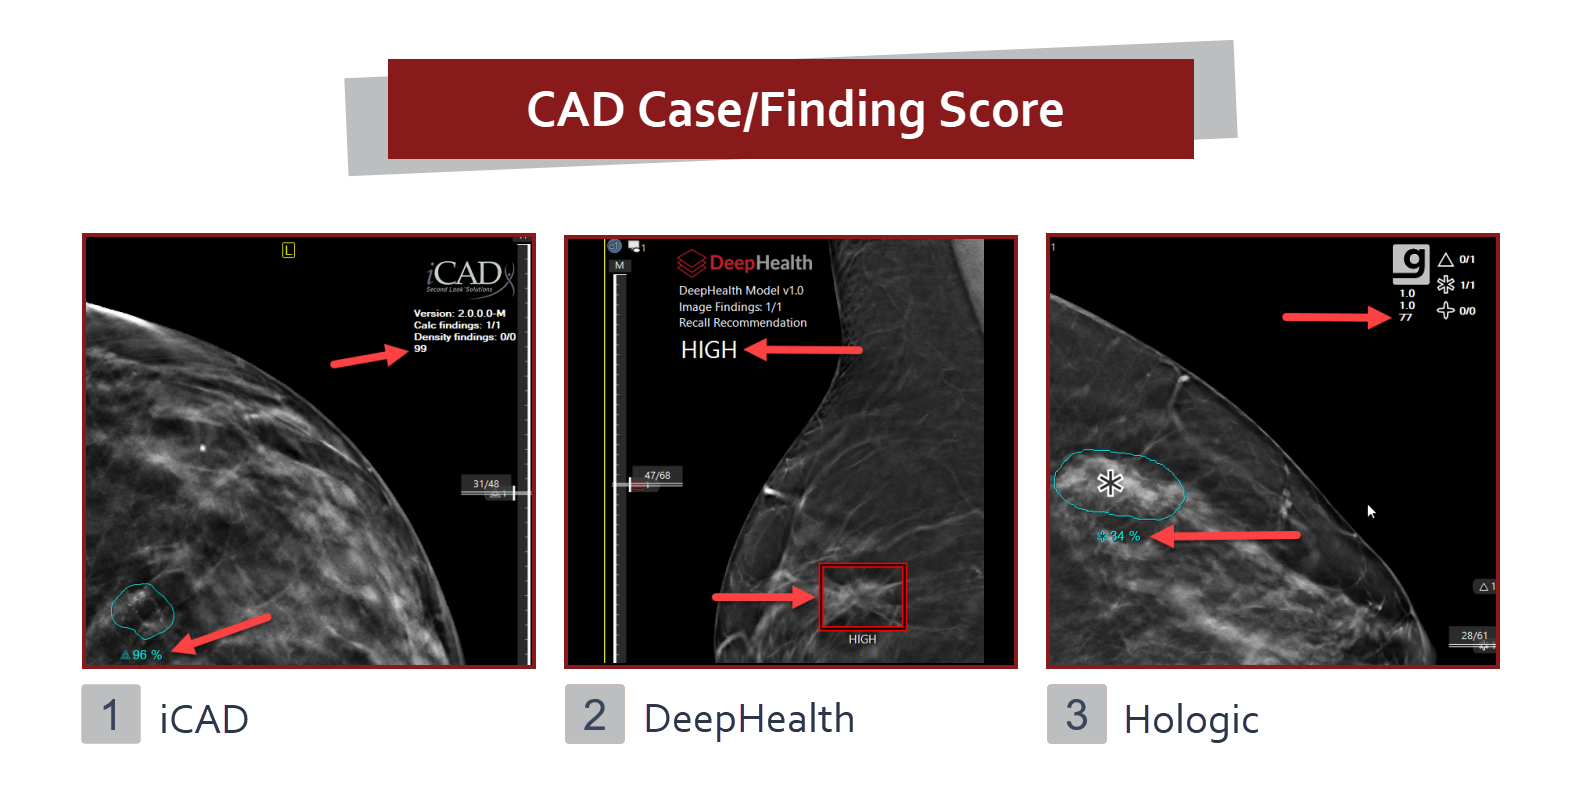

A CAD marker provides computer-aided diagnosis to mammography images.

CAD Certainty Scores

Some CAD vendors provide case scores for each study and or finding. Case score can be found in the CAD header and an individual finding score can be found adjacent to the marking on the image.